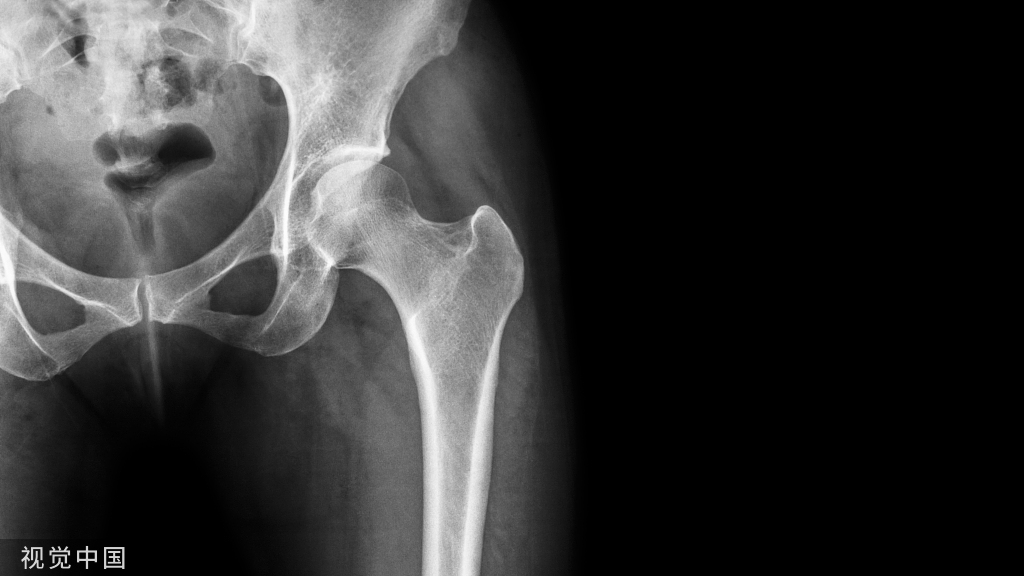

示例为44岁女性,糖尿病控制不良,扭伤导致踝关节双踝骨折,需手术固定。